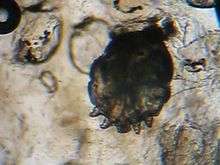

A photomicrograph of an itch mite (Sarcoptes scabiei) | |